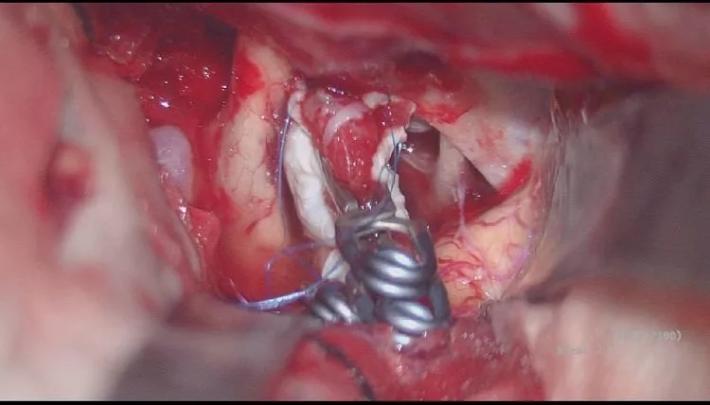

并行自752夹子上方向近端置742动脉瘤夹一枚,并列自硬膜补片外侧夹闭BBA,手术顺利! 那么脉前A怎么保全呢?

脉前A的保留是术中的一个难题,我们采取硬膜瓣半侧开叉(黄箭头),让脉前A(粉红箭头)由开叉处穿出,避免包裹夹闭后扭曲压迫而致闭塞,术中拟在阻断IcA颅外段与同侧A1的低灌注压状态,采用“L”型异形夹多可顺利夹闭BBA,保留后方脉前A通畅!